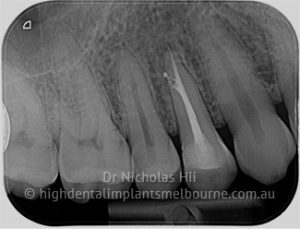

Root canal treatment is required to save the tooth when the pulp, which houses the blood and nerve supply to the tooth, becomes infected due to decay or a traumatic injury.

It involves removing the infected pulp by using specialised instruments that clean and shape the interior of the tooth. During this process, antimicrobial agents are used to flush the tooth to kill bacteria harbouring inside.

Once the cleaning process has been completed, the tooth’s interior is sealed with a root filling to prevent bacterial invasion and to restore the strength of the tooth. When a significant amount of tooth structure has been lost due to decay or the process of root canal treatment itself, a crown is recommended which acts like a helmet to protect the tooth.